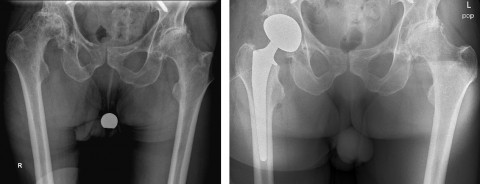

In der Schulthess Klinik diagnostizierten wir in der Abteilung Hüftchirurgie in der durchgeführten Röntgenuntersuchung (Beckenübersicht und Hüfte axial) eine weit fortgeschrittene Coxarthrose rechts. Der Femurkopf (Hüftkopf) war deformiert und bereits subluxiert . In der klinischen Untersuchung zeigte sich eine stark eingeschränkte, schmerzhafte Beweglichkeit. Mit dem Patienten und seiner Frau besprachen wir die Befunde und Therapiemöglichkeiten. Aufgrund der Beschwerden sowie der zunehmenden Immobilität stellten wir die Indikation für einen prothetischen Gelenkersatz.

Die Operation erfolgte durch Prof. Dr. med. Michael Leunig, Chefarzt Hüftchirurgie, über einen direkten, vorderen Zugang zum Hüftgelenk. Bei diesem Zugang werden die wichtigen beckenstabilisierenden Hüftmuskeln geschont und eine rasche Rehabilitation ermöglicht. Es handelt sich hierbei um eine standardisierte Routineoperation. Bei genanntem Patienten musste jedoch aufgrund der komplexen Situation mit Morbus Parkinson, Pisa Syndrom und Sturztendenz besonders auf eine maximale Stabilität des Kunstgelenkes geachtet werden. Daher erfolgte die Implantation einer dual-mobilen Pfanne. Dieses System kombiniert einen erweiterten Bewegungsumfang mit geringerer Luxationsrate. Da der Patient eine gute Knochendichte aufwies, konnten wir die Implantate zementfrei fixieren und somit das Risiko einer Knochenzementreaktion vermeiden.

Intraoperativ achteten wir klinisch wie auch radiologisch auf eine korrekte Ausrichtung des Schaftes sowie der Pfanne, um einen möglichst grossen, stabilen Bewegungsumfang zu erreichen. Zudem legten wir grossen Wert auf eine minutiöse Blutstillung, um den Blutverlust so gering wie möglich zu halten, und arbeiteten bei implantiertem Neurostimulator mittels Bipolar.